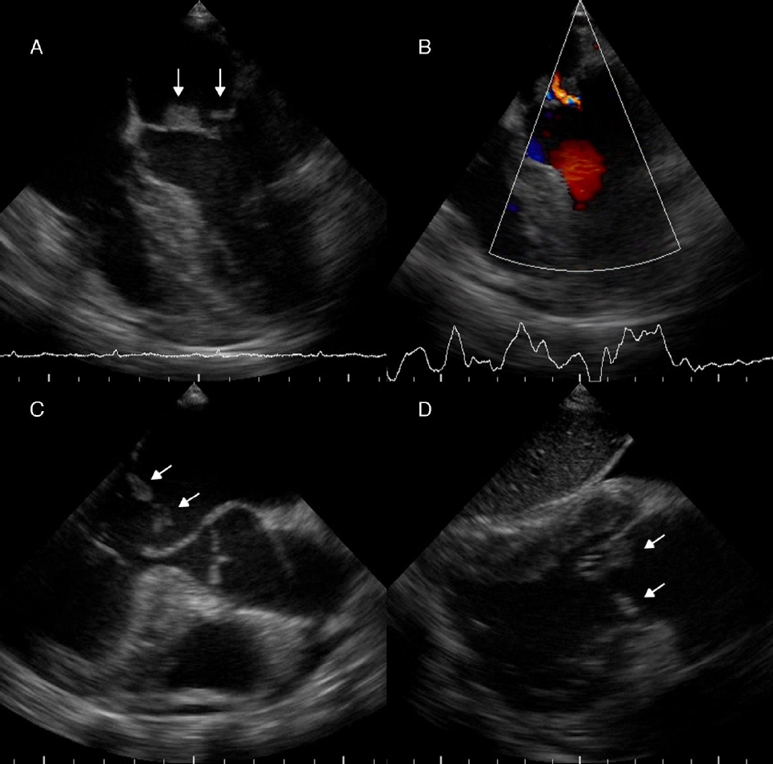

Paciente mujer de 28 años de edad, quien presentó 3 semanas antes de su ingreso, disnea a moderados esfuerzos que progresó a ortopnea. Una semana antes de su ingreso presentó epigastralgia, la cual no se calmó a pesar de diversos tratamientos indicados en centros de salud de su localidad, por lo cual fue trasladada al Servicio de Emergencias del Hospital Universitario de Los Andes. Tiene como antecedentes LES y SAF diagnosticado a los 15 años de edad, sin tratamiento en el momento de la evaluación, por abandono voluntario de la paciente. Presentaba una herida traumática en la pierna izquierda, la cual ameritó injerto de piel en el año 2005 y que, al momento de su ingreso, se encontró sobreinfectada. El servicio tratante solicitó valoración por cardiología, y se realizó ecocardiograma transtorácico (Fig. 1), en el cual se observó engrosamiento de las porciones distales de ambas valvas de la válvula mitral, que generaba imagen de bordes irregulares y condicionaba a insuficiencia leve. Se solicitó hemocultivo, el cual resultó negativo hasta 7 días después de la incubación, y se realizó ecocardiograma transesofágico (Fig. 2), en el cual se observaron imágenes ecogénicas, fijas, de bordes irregulares, adosadas a la superficie auricular de la valva anterior y posterior de la válvula mitral, de 14 × 9 mm y 8 × 5 mm respectivamente. Se solicitó un nuevo hemocultivo, el cual resultó nuevamente negativo. Además de ello la proteína C reactiva y la velocidad de sedimentación globular se encontraban dentro de límites normales, por lo cual no se inició antibioticoterapia. La paciente fue valorada por el servicio de reumatología, quienes determinaron que se encontraba con actividad lúpica e indicaron tratamiento inmunosupresor. Ante todos estos hallazgos clínicos y paraclínicos determinamos que las vegetaciones observadas en la paciente no eran debido a infección bacteriana, sino que concordaban con el diagnóstico de ELS.

Figura 2 Ecocardiograma transesofágico. A y B. Vista medio esofágica de 4 cámaras (modificada), en las que se observan imágenes ecogénicas en la superficie auricular de ambas valvas de la válvula mitral, de gran tamaño, de bordes irregulares, sésiles, en festones A2 y P2 (flechas), que con doppler color permite observar insuficiencia valvular leve. C. Vista medio esofágica de eje largo de la válvula aórtica (modificada), donde se observan ambas vegetaciones adosadas a la superficie auricular de las valvas de la válvula mitral (flechas). D. Vista transgástrica de 2 cámaras. Se observan vegetaciones en la superficie auricular de las valvas de la válvula mitral (flechas).

En el ecocardiograma se pueden observar masas valvulares o vegetaciones, y engrosamiento valvular. Las masas pueden variar de forma y tamaño, generalmente más de 2 mm de diámetro, con bordes que usualmente son irregulares, adheridas firmemente a la superficie valvular auricular o ventricular, sin exhibir movimientos independientes. Las válvulas que se afectan con mayor frecuencia son las del lado izquierdo. Cuando la válvula mitral se encuentra afectada, las vegetaciones se pueden extender al aparato subvalvular y al endocardio adyacente a la valva6. En este caso las masas sobrepasaban los 5 mm, y se encontraban sésiles en la superficie auricular de la válvula mitral, sin extenderse al aparato subvalvular, y como se vio en el ecocardiograma transesofágico había insuficiencia mitral leve.